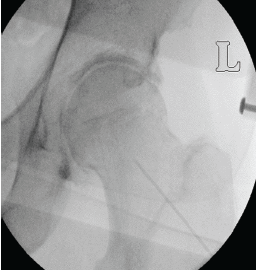

Intramedullary Fibular Nail Fixation in an Elderly Patient with a Comminuted Weber C Ankle Fracture: A Case Report

Ajith Kumar Kannan , Anisha Tyagi , Johnny Dong , Elias Logothetis , Jay Bhuta , Rahul Mittal